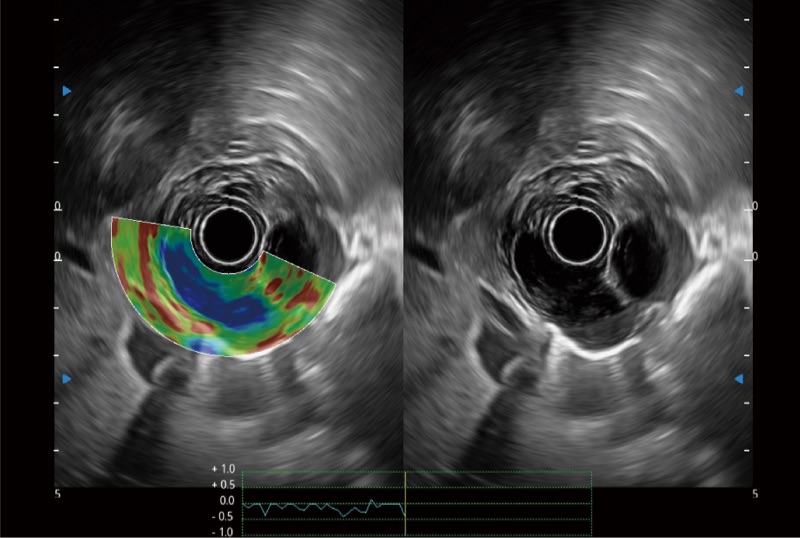

肝左叶和肝静脉的横截面

位移矫正技术

不可靠区域自动剔除

弹性定量分析软件